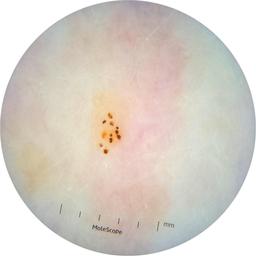

ISIC_6363669

Information

923 x 923

Clinical

Field Value

acquisition_day 264

age_approx 65

anatom_site_1 Trunk

anatom_site_2 Anterior trunk

anatom_site_general anterior torso

concomitant_biopsy False

diagnosis_1 Benign

diagnosis_confirm_type single image expert consensus

family_hx_mm True

image_manipulation instrument only

image_type dermoscopic

lesion_id IL_2591344

patient_id IP_1322385

personal_hx_mm True

sex female